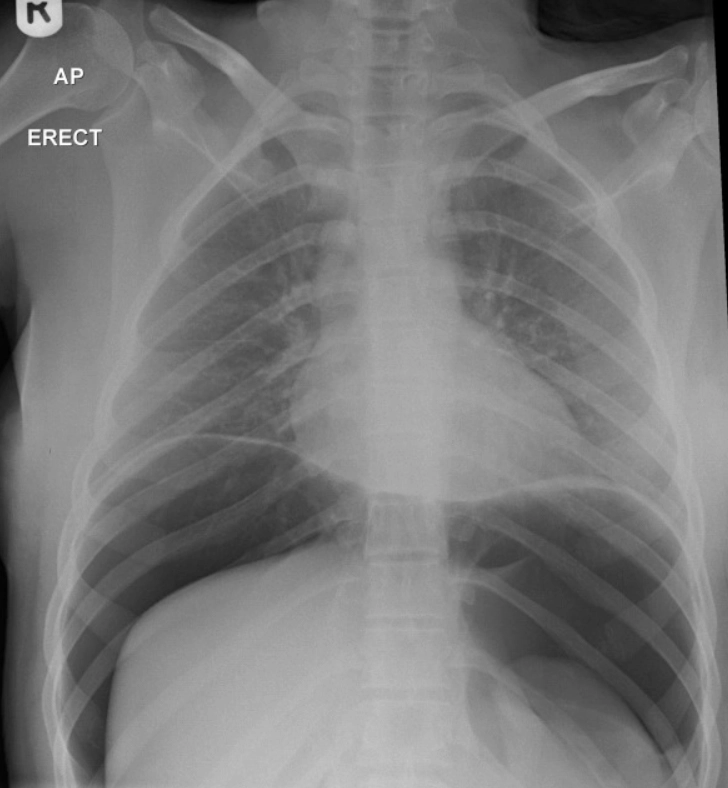

한 전문가는 “액체질소가 입이나 식도를 통해 위장으로 들어가면 순식간에 기체로 변하며 부피가 수백 배 이상 팽창한다”며 “이 과정에서 위장이 풍선처럼 부풀어 오르다 압력을 견디지 못하고 터지는 ‘위장 파열’이 발생할 수 있다”고 강조했다.

실제로 과거 영국에서는 18세 소녀가 생일 파티에서 액체질소가 든 칵테일을 마셨다가 위장에 구멍이 뚫려 위 전체를 적출하는 대수술을 받은 일이 발생하기도 했다.